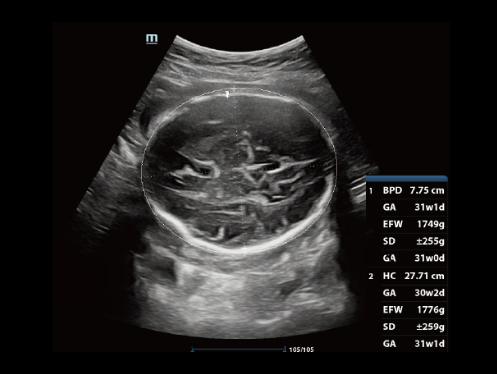

ImĂĄgenes clĂnicas